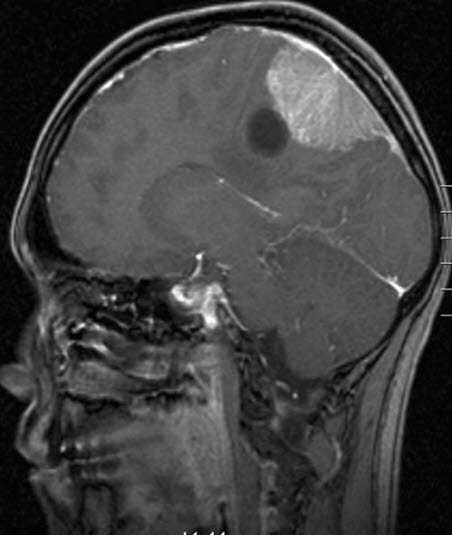

Meningeom med cyste, sagittalt snitt

Gjengitt med tillatelse av Radiologisk avdeling, Universitetssykehuset Nord-Norge